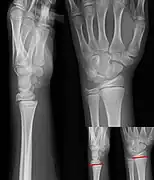

Salter–Harris II fracture of ring finger proximal phalanx. -